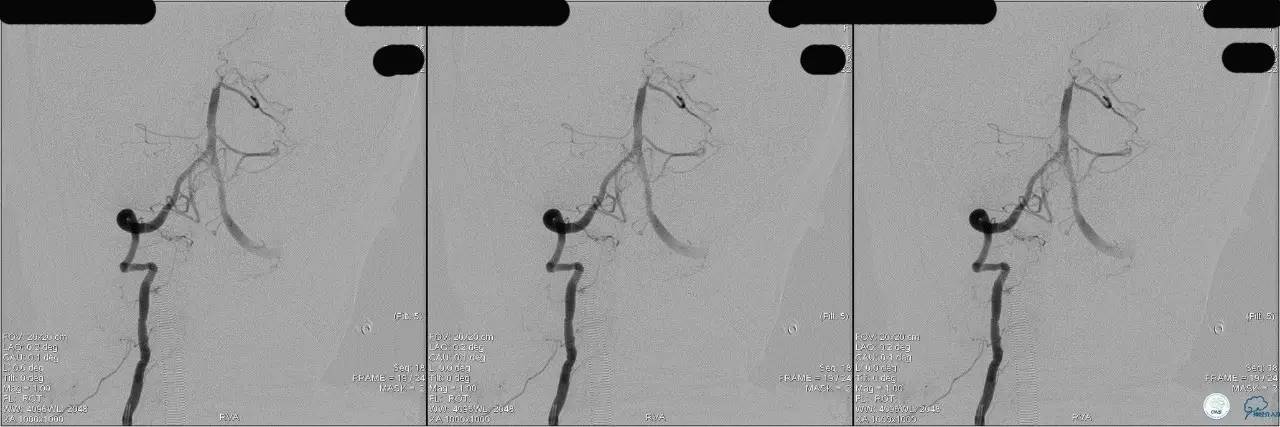

》DSA资料(左侧颈动脉)

》DSA资料(右侧颈动脉)

》DSA资料(左侧椎动脉)

》DSA资料(右侧椎动脉)